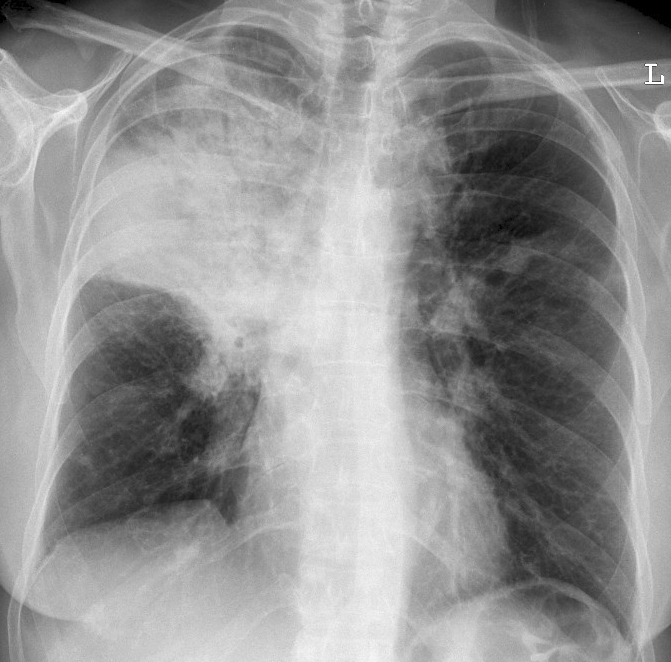

Case 13 RUL pneum PA